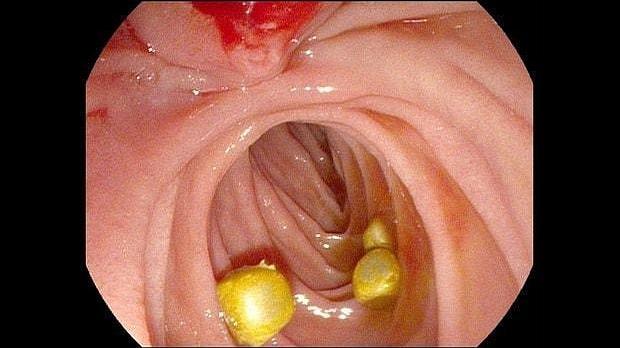

Здравствуйте. Пациентка, 32 года. Поступила на хирургическое отделение с диагнозом ЖКБ: холедохолитиаз. По данным МРТ: ЖКБ, множественные мелкие конкременты холедоха. При дуоденоскопии выявлено наличие вклиненного конкремента большого дуоденального сосочка. Выполнена прекатсфинктеротомия, получено 3 конкремента, диаметром около 0.4-0.5 см. Далее канюляция холедоха проволочным папиллотомом, выявлены многочисленные конкременты холедоха. Выполнена литоэкстракция ревизионным баллоном (на последнем фото окклюзионная холангиография - в просвете холедоха не конкременты, а пузырьки воздуха)).